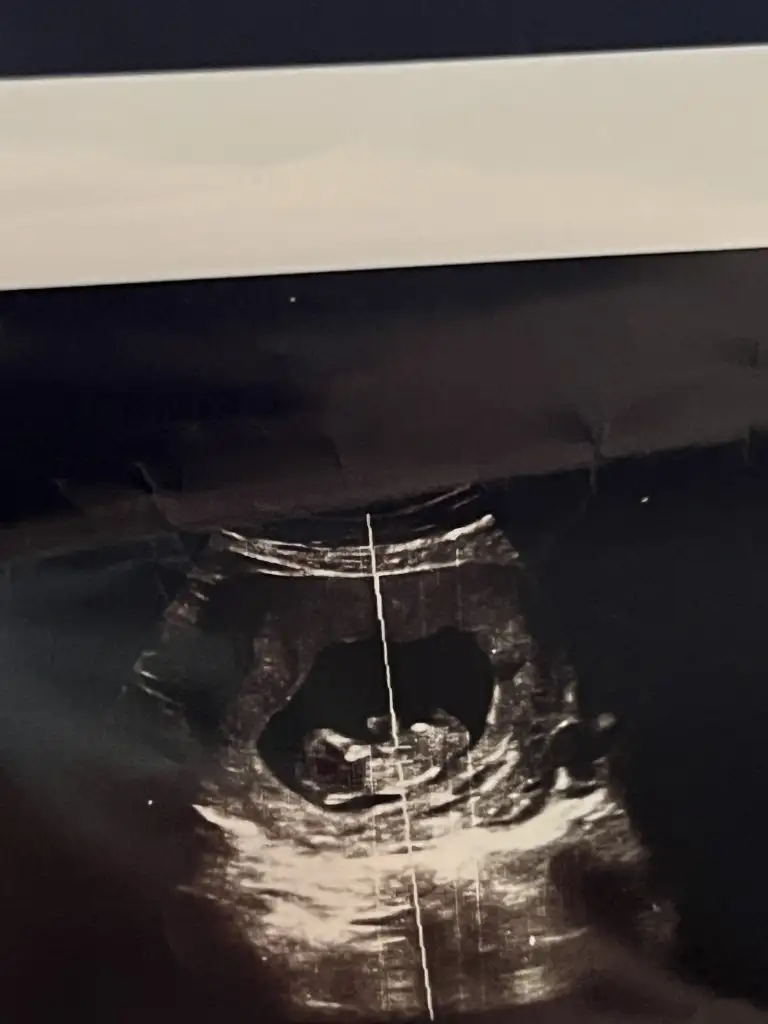

Merhaba öncelikle hayırlı olsun sağlıkla gelsin bebisiniz 😊🙏🏻🧿 bize de 12. Haftada özelde kesin kız dedi doktor dun devlette doktora gittiğimizde henüz göstermiyor dediler bizimde değişir mi sizin gibi fotoğrafları ekliyorum ilk fotograf 12. Hafta bacak arası fotoğrafı ikinci fotoğraf 15+1 yorum yapabilecek olan varsa çok sevinirim